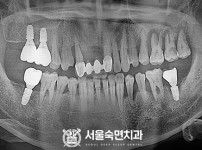

임플란트-전후사진2

임플란트-전후사진3